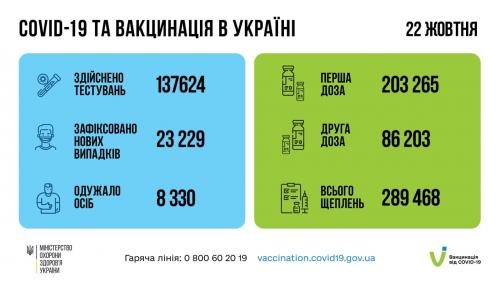

МОЗ: Уперше з початку пандемії було зроблено понад 100 тисяч ПЛР-досліджень за добу